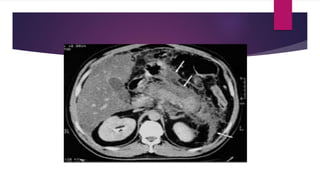

 CT: Not necessary if only a mild attack

 CT advised when

 Diagnostic uncertainty

 Severe acute pancreatitis to diff from interstitial and necrotizing

pancreatitis

 Patients with MODS and progressive sepsis

 Localized complication is suspected

 CT: Notnecessary if only a mild attack  CT advised when  Diagnostic uncertainty  Severe acute pancreatitis to diff from interstitial and necrotizing pancreatitis  Patients with MODS and progressive sepsis  Localized complication is suspected